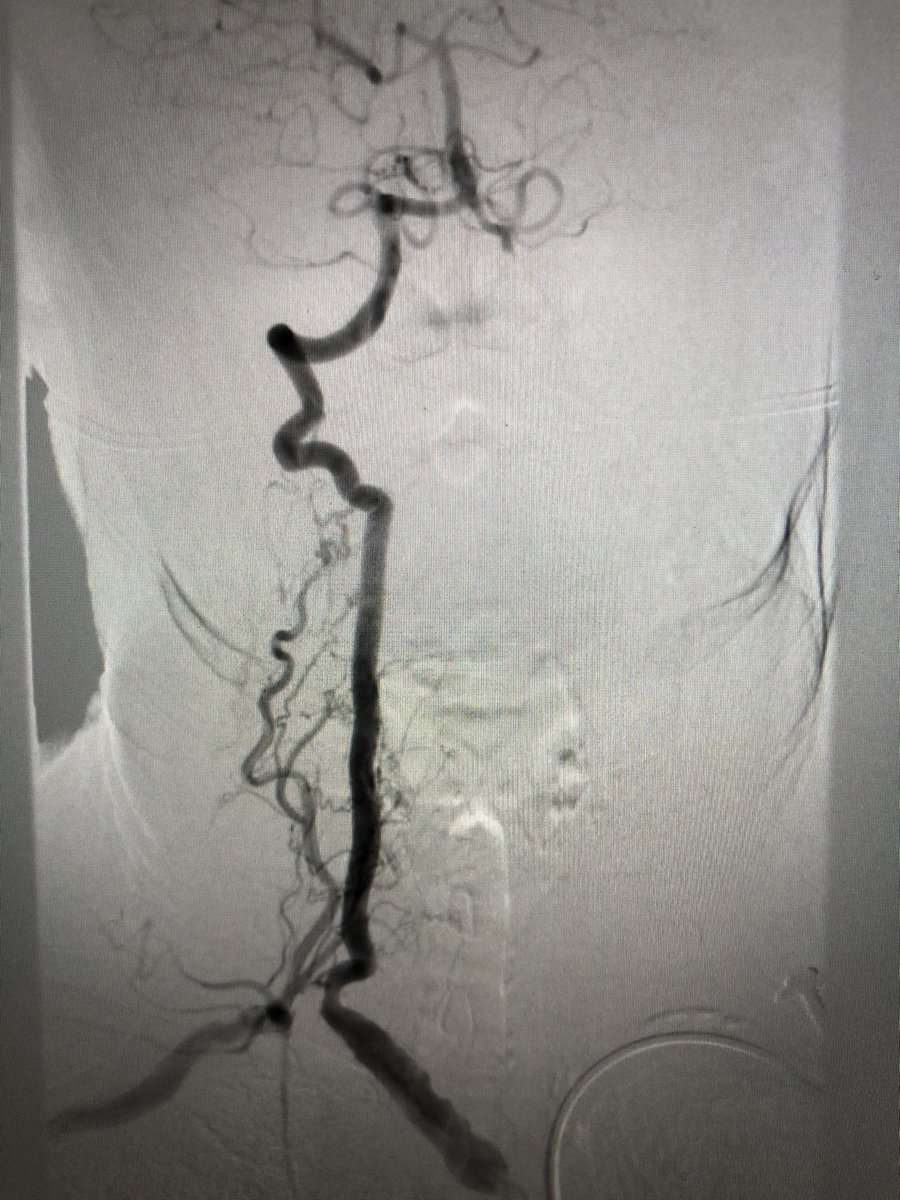

7.4 cm AAA w/ bilateral CIA aneurysms successfully treated with EVAR and bilateral iliac branch devices w/ coil embolization of the anterior branch of the R IIA. Even the daily disruption related to COVID can’t diminish the satisfaction of a case coming together #SCAIPAD #TCAVI